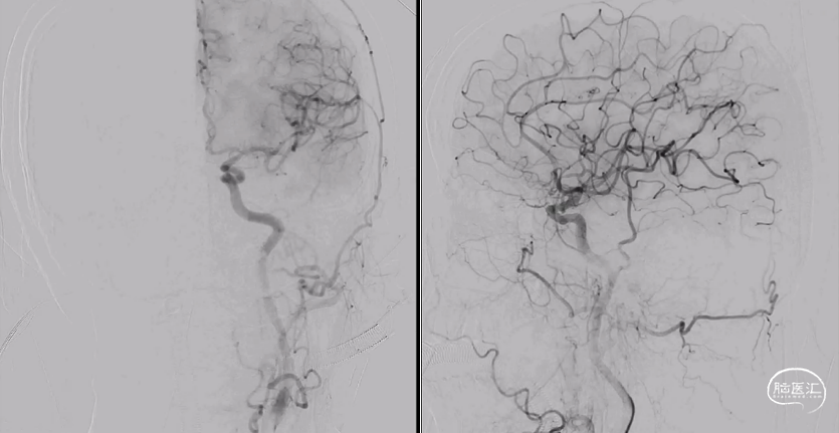

术中将导引导管置于左侧颈内静脉,并引导至左侧岩下窦,Echelon-10微导管经由髁静脉超选至瘘口处。微导管到位后再次进行双容积三维后处理,验证微导管到位位置为术前所判断的瘘口处(图4),随后在瘘口放置一枚弹簧圈,并在阴性路图下注入Onyx胶0.8ml(图5)。复查造影见瘘口完全栓塞,异常引流彻底消除(图6)。

栓塞术后即刻CT未见颅内出血或Onyx胶异位栓塞。麻醉复苏后患者诉耳鸣消失,未诉其他不适,查体无新发神经系统体征。术后第二日,复查CT未见异常(图7),患者顺利出院。

患者术后半年于当地医院复查血管造影,提示瘘口完全栓塞,未见复发(图8)。